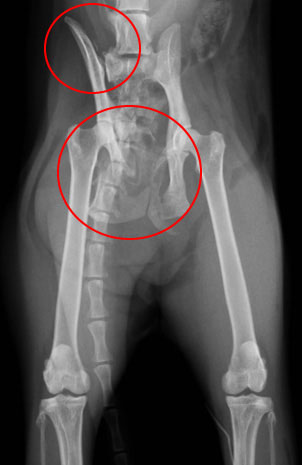

手術前のレントゲン写真です。

赤い丸で示した大腿骨頭がレッグカルベペルテス病

に侵された場所です。

手術後のレントゲン写真です。

大腿骨頭切除術を行ったレントゲン写真です。